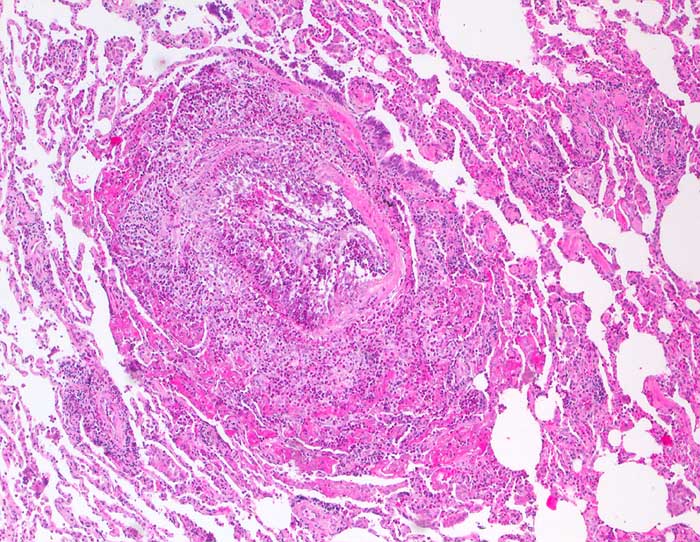

Churg Strauss Vaskulitis

Die zytologischen Veränderungen bei der Churg Strauss Vaskulitis entsprechen den Veränderungen bei allergischem Asthma bronchiale. Im Vordergrund steht eine massive Vermehrung eosinophiler Granulozyten. Histologisch findet sich zusätzlich eine nekrotisierende eosinophile Vaskulitis.